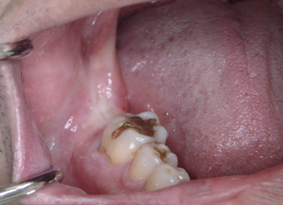

DSC01256.JPG

術前です

右下の一番奥に埋め込みます